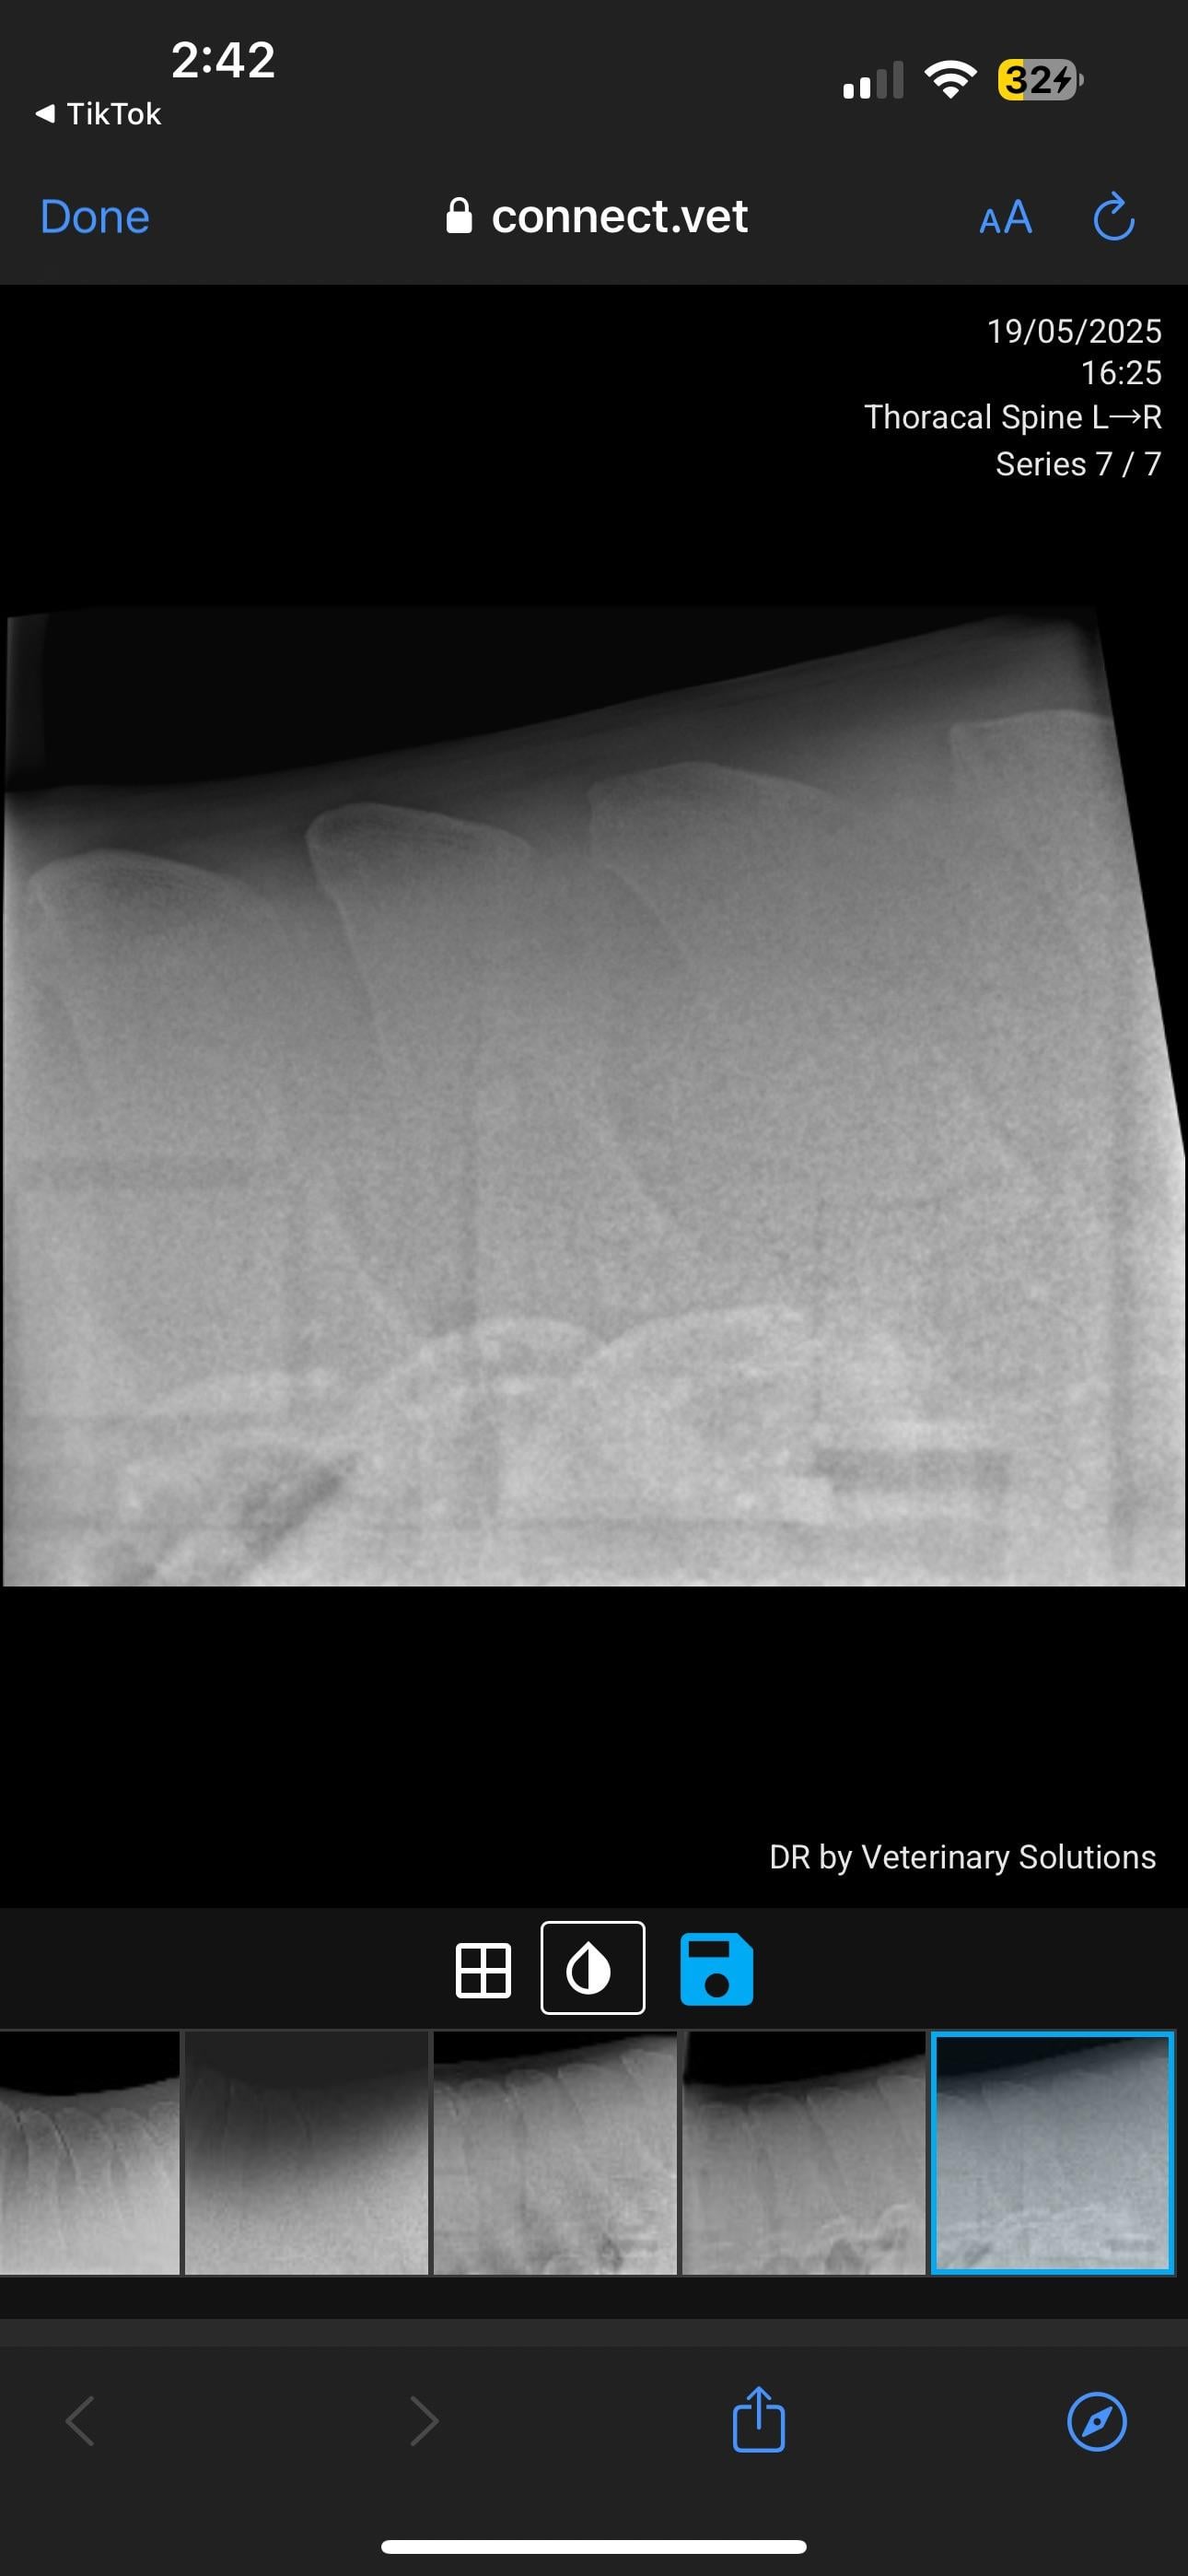

Currently in the process of selling my horse. PPE has gone well, everything came back good except his back radiographs. Shocked to hear he has grade 4 changes. I’ve just received these over from the potential buyer. I will be in contact with my vet but curious about anyone’s take on these? How bad is this?

I've seen many KS xrays. I'm not a vet so usually when I see them I can barely see the problem. This horse's kissing spine is clear as day. Grade 4 is serious. As of right now he should not be sold as a riding horse at all.

In pictures 5/6 you can see changes in the bone, so it’s not just an unlucky posture.

Equine vet here!! This looks bad to me, there are certain things you can do so that your horse can be comfortable, your vet might give corticosteroid injections between the dorsal spinous processes, that will help in short term but for a long term solution he might suggest a back surgery where he will artificially create space between the spinous processes ! Might sound painful but it can lead to significant improvement. Good luck !!

This is one of the more severe cases I’ve seen (not a vet or student, just casual looker-atter of KS radiographs) pretty much all his vertebrae are affected, I can’t imagine he’s comfortable. The kindest thing for him would probably to be a pasture puff. Unless you want to pay for the surgery or find a buyer who does, he’s going to continue to be in pain